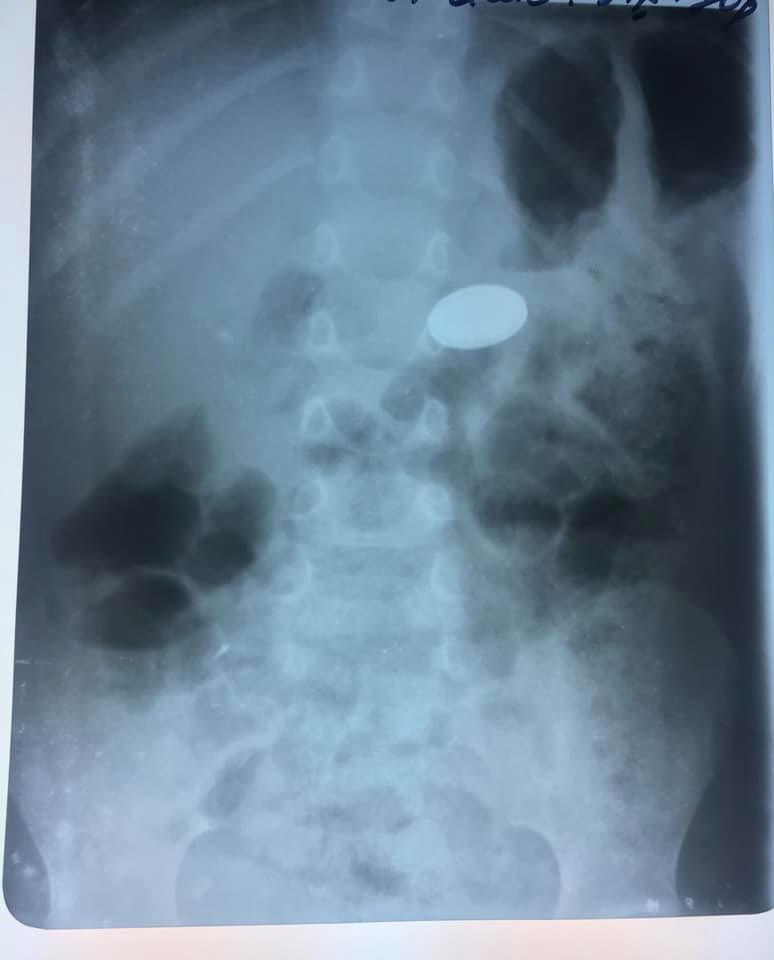

У львівській лікарні ОХМАДИТ 3-річній дівчинці з Червонограда успішно видалили батарейку, яку вона проковтнула.

Як пише «Четверта студія», на сторінці Львівської обласної дитячої клінічної лікарні ОХМАДИТ у ФБ повідомляється, що коли 3-річна дівчинка з Червонограда ковтнула батарейку, то не призналася мамі, а сказала лише, що “щось проковтнула”. Коли мама обстежила кімнату, то виявила, що у настільних вагах бракує однієї батарейки.

«Жінка вчасно встигла до нас приїхати і команда лікарів видалила нехитру забавку зі шлунка маленької. Діставали батарейку лікарка-ендоскопіст. Лікарі обійшлися без відкритої операції, за допомогою ендоскопа дістали стороннє тіло. Це не так просто зробити, адже лікарі працюють на відстані, батарейка слизька і зісковзує, доводиться робити кілька спроб її витягнути. Дівчинці пощастило, адже батарейка не встигла наробити біди», – зазначається у повідомленні.

“Дівчинку ми прооперували ендоскопічно під загальним наркозом. Батарейку встигли дістати зі шлунка, вона не встигла зашкодити маленькому шлунку”, – зазначила лікар-ендоскопіст ОХМАТДИТу Марта Лучак.